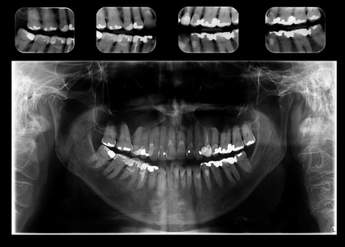

RADIOGRAFIA PANORÂMICA

Radiografia extraoral 2D que produz uma única imagem com visualização ampla dos maxilares.

Comumente usada como imagem inicial complementar para avaliação de traumatismos, localização de terceiros molares, patologias extensas, lesões grandes conhecidas ou suspeitas, desenvolvimento dentário (especialmente na dentição mista), retenção dentária ou do ápice radicular (em pacientes edêntulos) e anomalias de desenvolvimento. É o exame complementar mais solicitado por todas as especialidades.